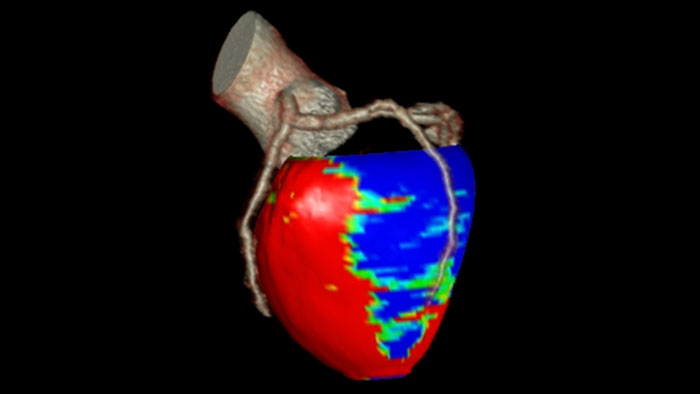

CT Dynamic Myocardial Perfusion (DMP)

Dynamic color maps provide an assessment of myocardial risk

Provides automatic and manual tools to help visualize and assess signal intensity differences (in Hounsfield Unit) focusing on the left ventricular myocardium, providing quantitative myocardial perfusion measurements for CT images.

Benefits

- Supports axial, ECG-gated CTA images, consisting of multiple time shots within the same acquisition of the myocardial region over time (i.e. dynamic CT scans), after an injection of intravenous contrast.

- Automatic and manual tools providing quantitative myocardial perfusion parameters such as: Peak Enhancement, Time To Peak, Perfusion and Blood Volume, and provides color maps representation of the results and graphical representation of intensity curves.